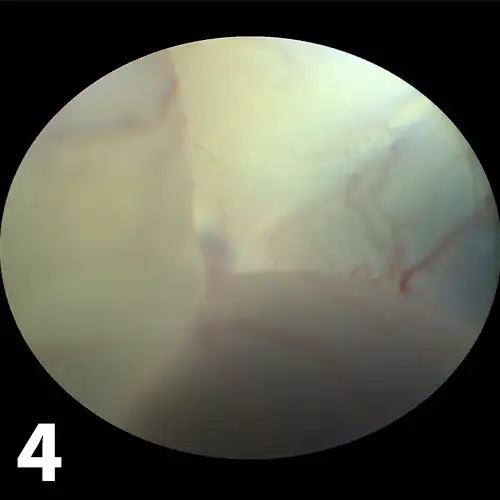

• A detached retina can be seen as a vascular, white-gray veil behind the lens (Figure 4). Varying degrees of intra- or subretinal hemorrhage may be seen. When the fundus cannot be seen (eg, because of severe corneal edema or hyphema), the detachment may be demonstrated by ultrasound. Rhegmatogenous retinal detachments, in which liquified vitreous enters the subretinal space through a retinal hole, are usually primary. No detailed evaluation is required, and patients can be referred to a specialist for retinal reattachment surgery if indicated. Other types of retinal detachments may be caused by systemic hypertension, systemic infections, or vascular diseases. These require a full systemic evaluation. Successful treatment of the primary cause may cause retinal reattachment and restored vision.6,7